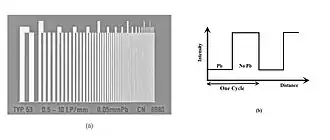

The maximum spatial resolution of an imaging system can be readily obtained by imaging a resolution test object - an example of which is shown in Figure 6.5, panel (a). The test object consists of narrow parallel slits in a lead sheet at spacings which decrease to beyond the maximum resolution of the image receptor. The minimum spacing resolved in images is called the Limiting Spatial Resolution and can be determined to be about 3.5 line pairs/mm from the figure.

Note that the width of each slit in the test object is the same as that of the adjacent piece of lead, so that the radiation intensity transmitted through the test object can be considered in profile to be represented by a square wave - see panel (b). A Spatial Period (usually measured in mm) can be used to characterize this square wave and is equal to the width of one line pair, i.e. the width of a slit plus its adjacent piece of lead. Its reciprocal is called the Spatial Frequency, which is generally expressed in line pairs/mm (LP/mm) or cycles/mm.